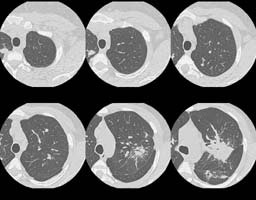

HRCT images:

(Click small pictures to view larger radiographs)